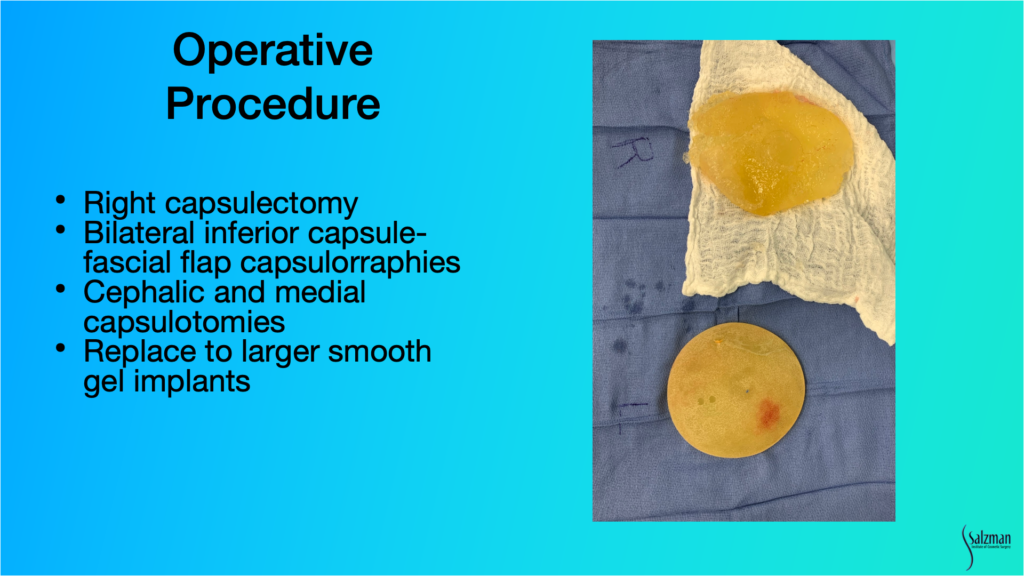

And that’s what we did. We did a right capsulectomy, an inferior capsule, a fascial flap capsulorraphy, cephalic and medial capsulotomies, and we went to a smooth-walled device.

And here you can see this grossly broken implant. It looks just like it didon ultrasound. It’s in pieces, essentially, and so you have invagination of elastomeric shell within the goopy silicone gel. And here’s the opposite side which is an intact. It’s an Allergan 410, or a shaped implant. And that’s what happens with the stretch of the bottom half of the pocket. I always see that. Much more with the 468 or the saline version of the 410. But even with textured 410, you see that.